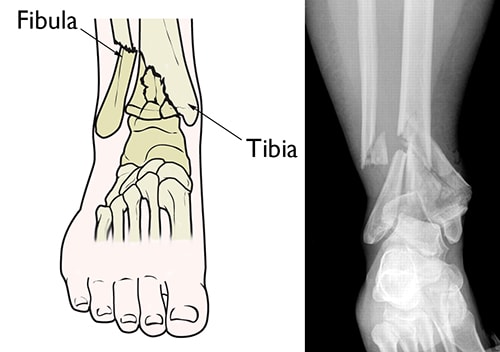

Illustration and x-ray of a pilon fracture

(Left) A pilon fracture often affects both bones of the lower leg. (Right) In this X-ray, both the tibia and fibula are fractured, and the pieces of bone are severely displaced.

Reproduced from Crist BD, Khazzam M, Murtha YM, Della Rocca GJ: Pilon fractures: advances in surgical management. J Am Acad Orthop Surg 2011; 19: 612-622.